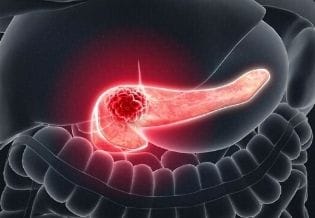

2026-02-10 07:46:34Pancreas

Pancreas is the leading biomedical journal dedicated to advancing knowledge on pancreatitis and its associated pathologies, with a focus on melatonin....